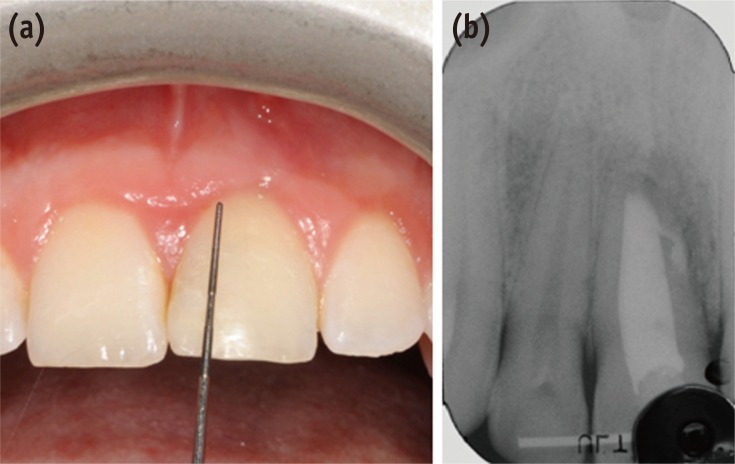

A clinical examination showed a moderate swelling on the vestibular side in the region of tooth #21, as well as the presence of a sinus tract in the same area, approximately 4 mm from the gingival margin (Figure 1). A narrow periodontal defect 7 mm in depth was present on the buccal side, as evaluated using a periodontal probe. A radiographic examination performed before surgery using both periapical radiographs and CBCT (J. Morita MFG Corp., Kyoto, Japan) revealed a root-end resection, a periapical radiolucency, and a widening of the periodontal ligament space at the mesial aspect of the root, although no hair-like fracture line radiolucency was noted in the tooth, except in the CBCT horizontal projection that showed an incomplete VRF 3 mm from the apex (Figure 2).